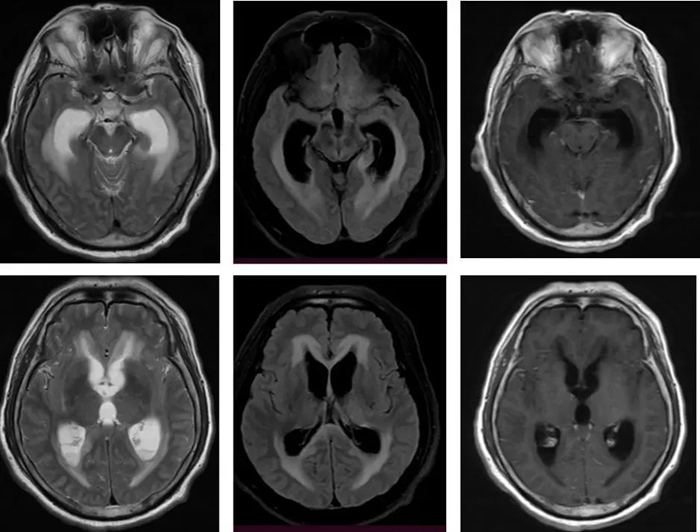

更令人担忧的是,患者在住院第3天病情急剧恶化:突发深度昏迷,血压下降,呼吸衰竭,不得不气管插管并转入神经重症监护室(NICU)。头部MRI显示脑内多发异常信号;室管膜及脑膜强化;幕上脑积水伴室旁水肿。

确诊李斯特菌脑膜炎并非易事。医生通常需要根据患者的年龄、基础疾病以及临床表现来判断其风险背景。例如,老年人、免疫力低下者伴有发热、意识改变时,便应引起高度警觉。脑脊液检查往往提示白细胞明显升高,蛋白含量升高,而葡萄糖浓度降低,形成典型的细菌性脑膜炎图谱。进一步的确诊则依赖于血液或脑脊液培养,这虽然可能需要数天时间,但一旦检出李斯特菌便可确诊。此外,脑部影像学检查如MRI也能帮助医生识别脑膜、脑干或脑室的异常变化,为早期干预提供线索。李斯特菌脑膜炎诊断挑战较大,但只要提高警惕,结合多项检查仍能及时识别。